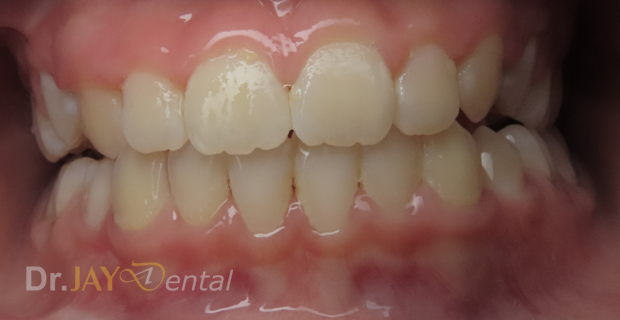

CASE 8

Patient had open bite and severe mouth breathing . At our office , patient went through myofunctional therapy , expansion of upper and lower jaw and aligning of teeth . No extractions needed and orthodontics was focused on airway, correcting habits and giving importance to the holistic health of patient. Patient’s mom extremely happy with the result.

Before

After